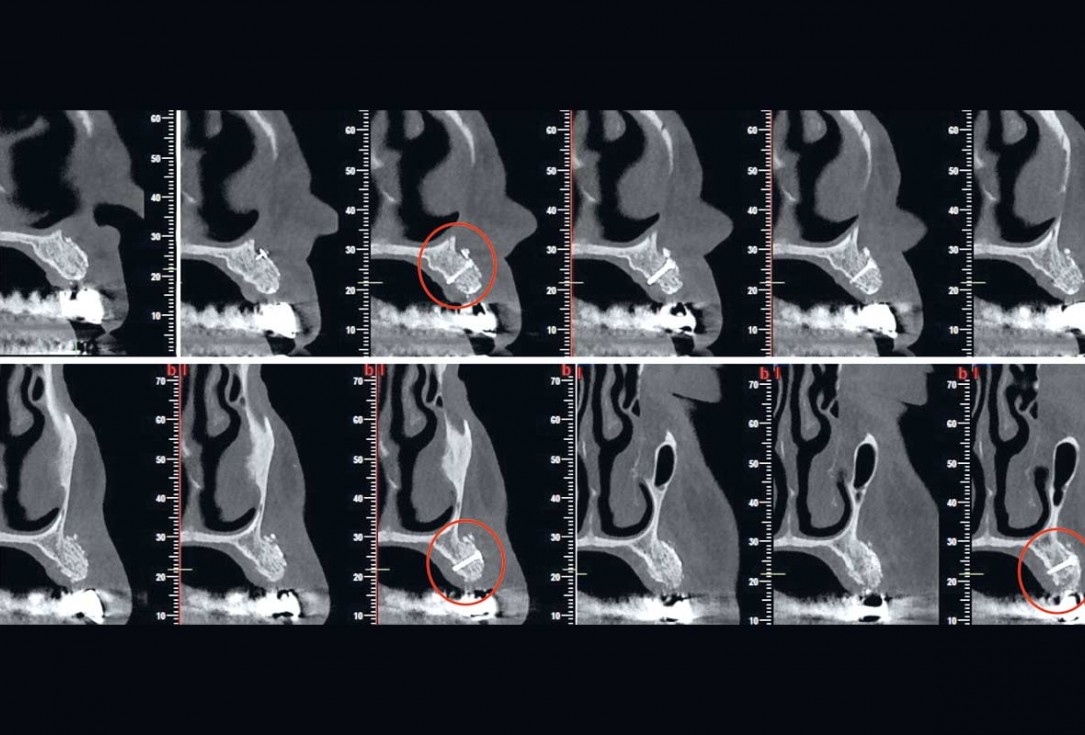

2/16 - CBCT data shows a horizontal and vertical bone loss in the anterior part of upper jaw

Reconstruction of Anterior Maxilla with maxgraft® bonebuilder – Dr. B. Han

16/16 - Stable outcome - 4 years after loading approx. 0.6 mm of bone loss was observed compared to 6 months after augmentation